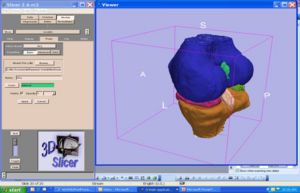

- 7.3 3D Slicer